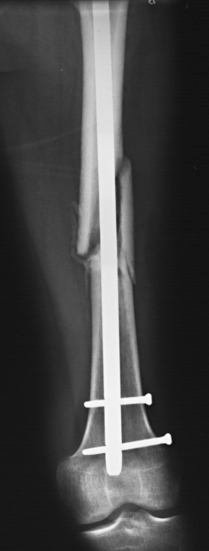

Structures shown: This projection shows the following: the inferior margin of the liver; the spleen, kidneys, and psoas muscles; calcifications; and evidence of tumor masses. If the image includes the upper abdomen and diaphragm, the size and shape of the liver may be seen (Fig. 28-15).

Fig. 28-15 Mobile AP abdomen radiographs. A, Abdomen without pathology. The entire abdomen is seen in this patient. B, Because of this patient’s increased body habitus, two crosswise (landscape) images of the abdomen were necessary to include all abdominal structures. Counting vertebral bodies ensures adequate overlap. Note large amount of free air indicative of a perforated bowel.